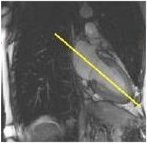

1. From an axial view, prescribe (green line indicates graphic location) and acquire a 2-chamber view.

Figure 1. Prescribe 2-chamber view